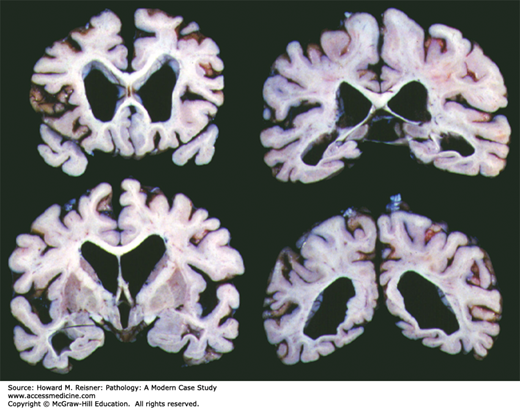

Alzheimer Disease Pathology

Alzheimer Disease Showing Pronounced Cortical Atrophy and Secondary Hydrocephalus Ex Vacuo. (Courtesy of Kinuko Suzuki, MD, Tokyo Metropolitan Institute of Gerontology; retired faculty, Department of Pathology and Laboratory Medicine, University of North Carolina, Chapel Hill, NC.)